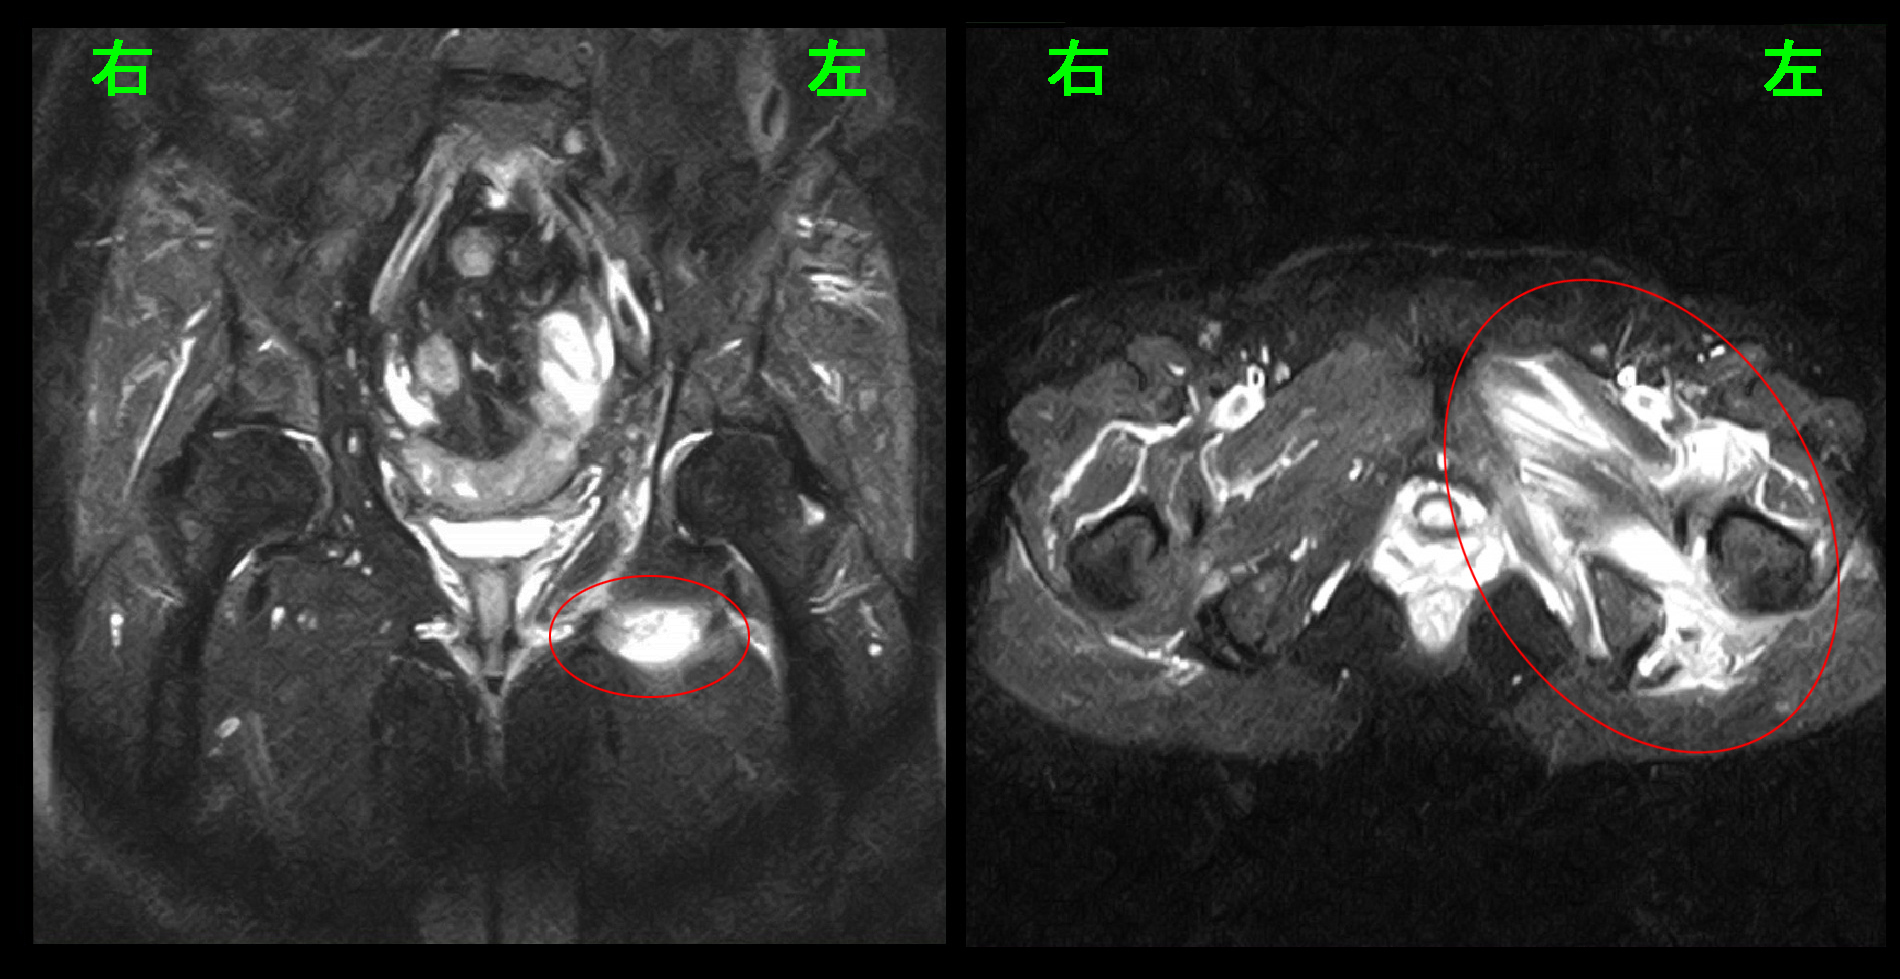

臀部痛・大腿部痛の患者さんでは股関節の異常の有無をチェックしますが、左股関節の異常を疑わせる理学所見がみられたため、股関節と腰椎のMRI検査を行いました。

赤丸が臀部痛の領域ですが、股関節のレントゲン像は異常はありません。

腰椎のMRI検査の所見は10か月前と変わりはありませんでしたが、股関節のMRI検査で左股関節周囲に広範な肉離れの所見(筋肉層の中に出血を示す白い所見)が確認されました。患者さんが10か月前と同じ腰に起因する痛みと感じても、その原因は全く別なものでした。

東京への往復の車の乗車と30分の畑仕事でこれほど広範な肉離れを発症することが疑問なので、改めて問診すると、患者さんは東京行き以後発症した腰痛は運動不足のせいと判断し、積極的に(おそらくは痛みがあったにも関わらず)いろいろな体操を行っていたということで、それが悪化の直接的原因と推察されました。